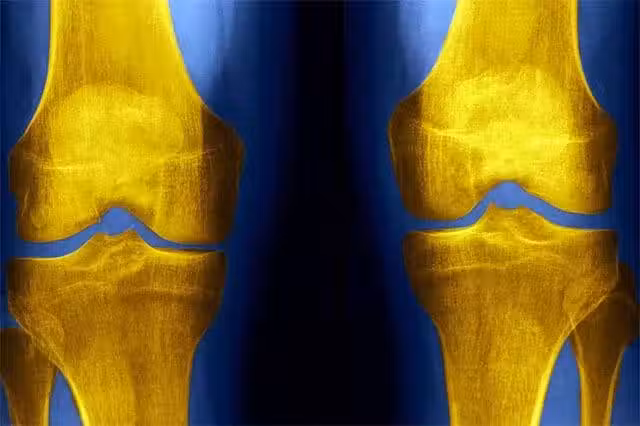

俗話說「人老腿先老」,好多病患者,都是風濕腿痛,平時不注意,積累到一定程度,就嚴重影響身體健康,治療起來,要用中藥配方產品,慢慢調理才有效。中老年朋友若掌握一些合理的膝關節的食療方法,記好多吃3種菜,少做3件事,能減少膝關節疼痛發炎,腿不老,人就更容易長壽。